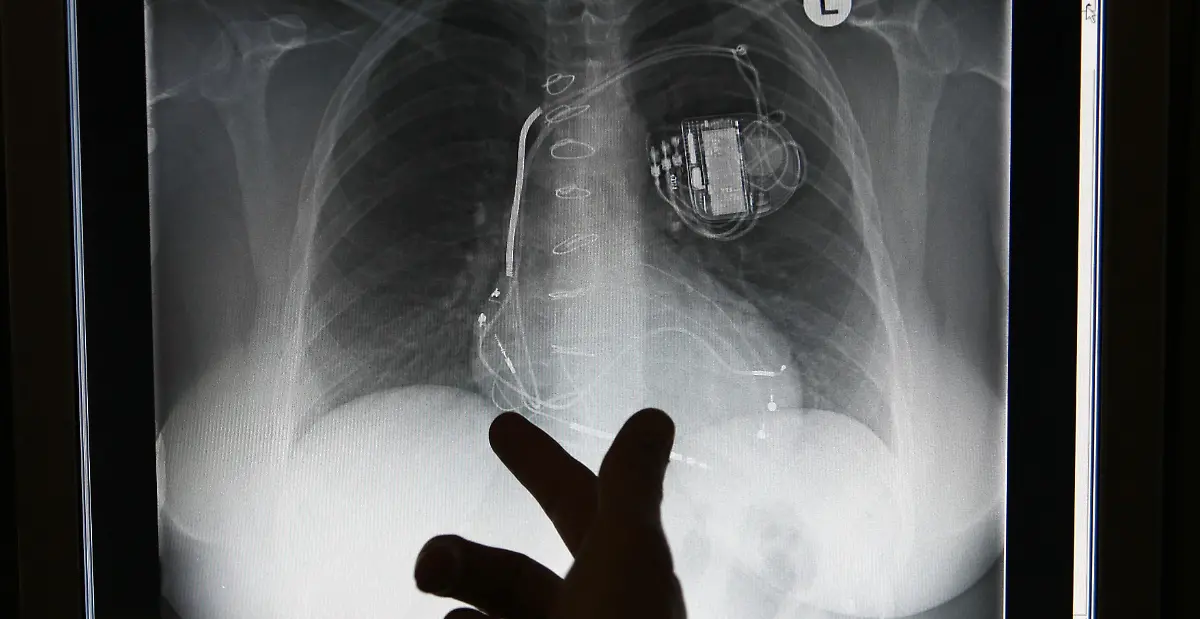

Nägel, Messer, TelefoneWas Röntgenstrahlen zum Vorschein bringen

Nicht immer zeigen Röntgenaufnahmen das, was man von ihnen erwartet. Oft kommt es zu Bildern, die selbst hartgesottene Betrachter zum Schaudern bringen - und der Wissenschaft Rätsel aufgeben.